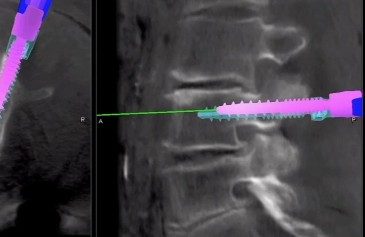

Mercy doctor's coat The Mazor technology gives skilled neurosurgeons precise imaging to assist in placing screws and performing spinal fusion.

Working with imaging services prior to surgery, Dr. Holekamp and his team used pre-operative scans of Kedney’s spine to program a plan for using the Mazor’s robotic guidance for placing screws and performing the fusion. Given the spine’s critical role in the human body, where even millimeter differences can be significant, this advanced technology enables surgeries that were previously impossible.